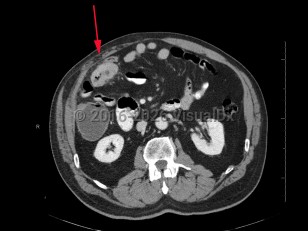

The most common sites of metastasis of colorectal adenocarcinoma are the liver and lungs; rarely, metastatic oral lesions occur. Cutaneous metastases of colon adenocarcinoma most commonly occur on the abdominal skin and may occur in the area of abdominal surgical scars.